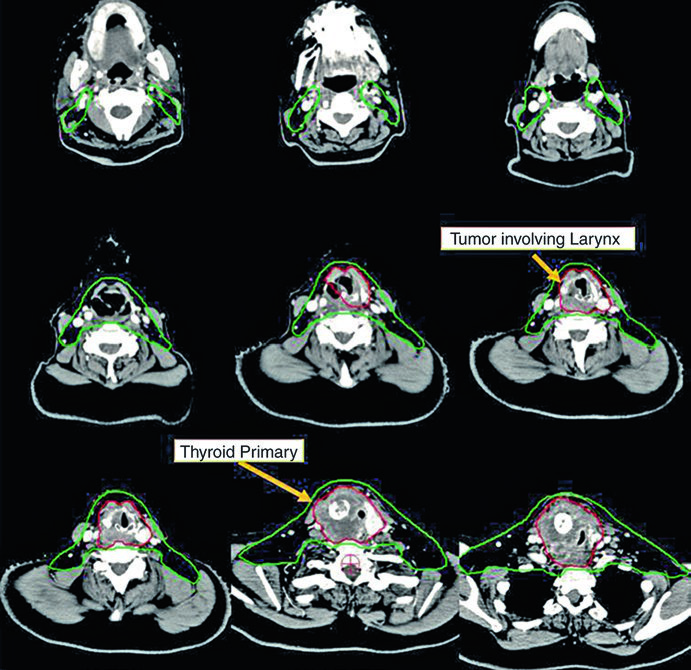

Caso 2 — Carcinoma anaplásico irressecável (Fig. 9.2): Mulher de 73 anos com carcinoma anaplásico de tireoide invadindo laringe, traqueia e esôfago. Recebeu quimiorradioterapia definitiva com doxorrubicina concomitante. O CTV70 Gy (vermelho) engloba toda a doença volumosa, e o CTV60 Gy (verde) abrange o risco subclínico. Detalhe importante: o manúbrio, que normalmente não é incluído no volume de risco, foi englobado neste caso específico por conta da doença volumosa anterior agressiva no pescoço. Essa decisão é atípica e deve ser individualizada — não se trata de protocolo, mas de resposta a uma apresentação clínica particular.

Esses dois casos ilustram a versatilidade da IMRT com dose-painting: o plano entrega simultaneamente 70 Gy ao volume de alto risco e 60 Gy ao volume subclínico, sem necessidade de boost sequencial. A escolha de doxorrubicina como quimioterápico concomitante no anaplásico reflete a agressividade dessa histologia e a necessidade de sensibilização ao tratamento, embora as opções sistêmicas tenham evoluído significativamente nos últimos anos.